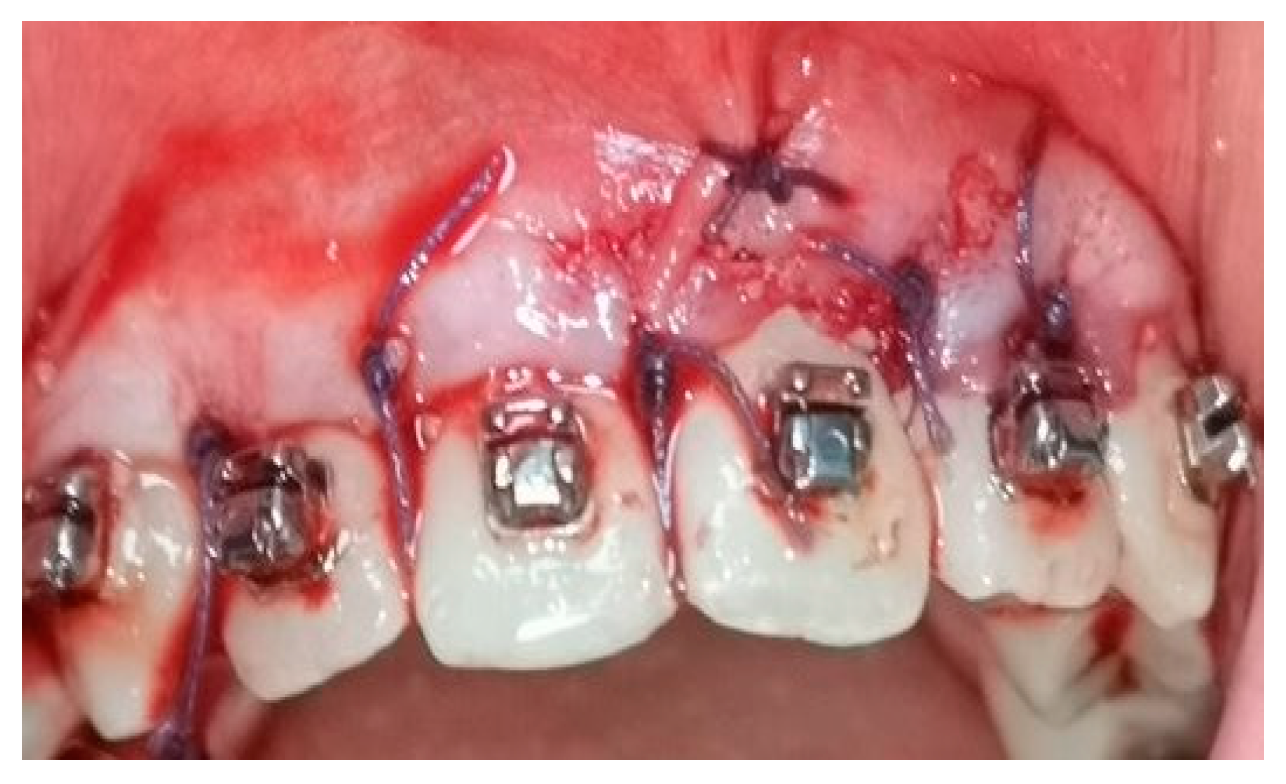

2.5. Surgical Phase